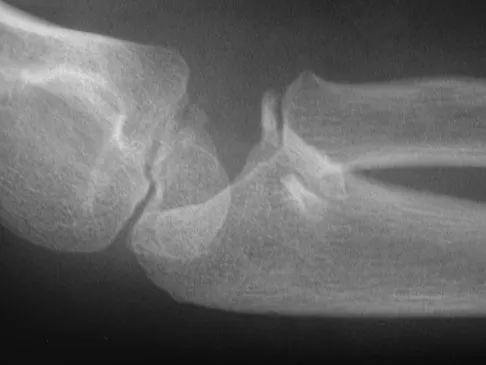

An 8-year-old girl injures her elbow playing soccer. After attempted reduction in the emergency department, radiographs of the elbow are shown in Figures 35a through 35c. What is the next most appropriate step in treatment?